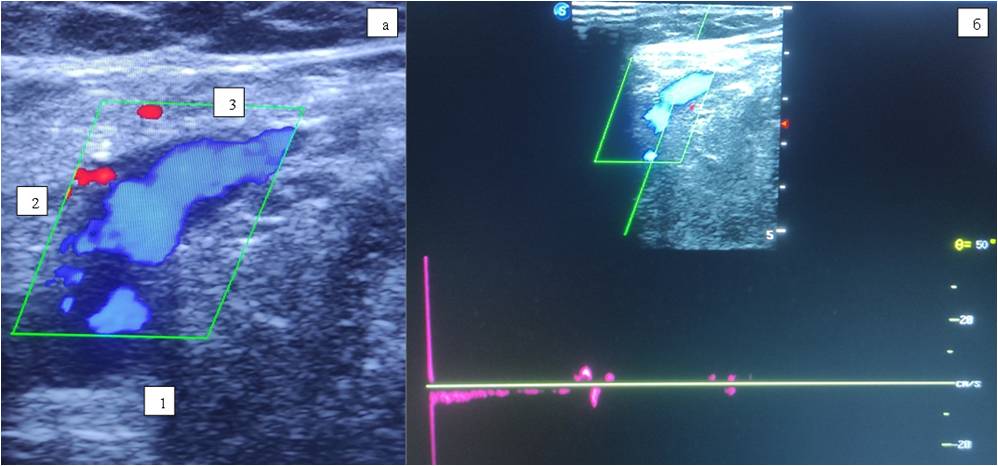

On a follow-up examination two years later: the patient notes a good cosmetic result of surgery. On DS, the GSV is patent, competent (Figure 4).

Fig. 4. Female patient Z., 35 years old. Control ultrasound scan of the vessels of saphenofemoral junction region in two years after the surgical intervention: a — color Doppler imaging mode; b — spectral Doppler mode.

Notes: 1 — common femoral vein, 2 — saphenofemoral junction, 3 — great saphenous vein.